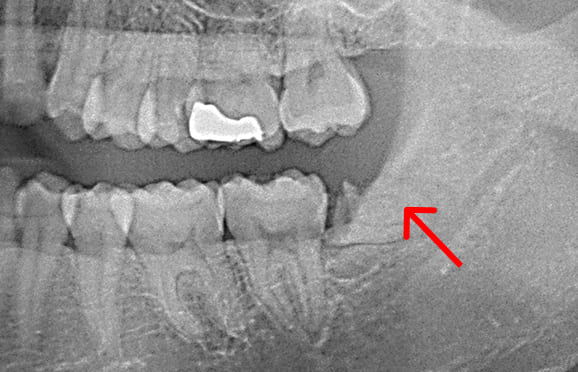

● 下の顎の親知らず抜歯 2回法

藤沢デンタルオフィスの親知らず抜歯

01 神経に近い位置に親知らずの根が存在

02 親知らずの頭の部分だけ抜歯

03 親知らずの根の部分が神経から離れる

下の顎の親知らずの抜歯では、神経の損傷リスクを考えて2回に分けて抜歯する場合があります。 また、麻酔が効きにくい場合にも、同様に2回に分けて抜歯します。